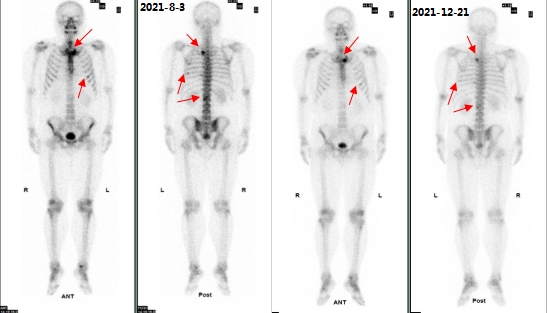

(病例三)患者,男 44岁,左肺下叶恶性肿瘤(T4N2M1c,IVB),纵膈继发性恶性肿瘤,胸膜继发性恶性肿瘤,骨和骨髓继发性恶性肿瘤。靶向药物治疗后为评估骨继发恶性肿瘤来诊。MIP图示:与2021-8-3日片比,2021-12-21日片示左侧第8后肋病灶放射性摄取明显减低,左侧第3后肋、胸骨柄片状放射性摄取范围减小,右侧第6前肋、L2椎体放射性摄取范围无明显变化。结论:与2021-8-3日片比:左侧第8后肋、左侧第3后肋、胸骨柄病灶骨盐代谢明显减低,提示肿瘤细胞活性减低;右侧第6前肋、L2椎体病灶骨盐代谢无明显变化。